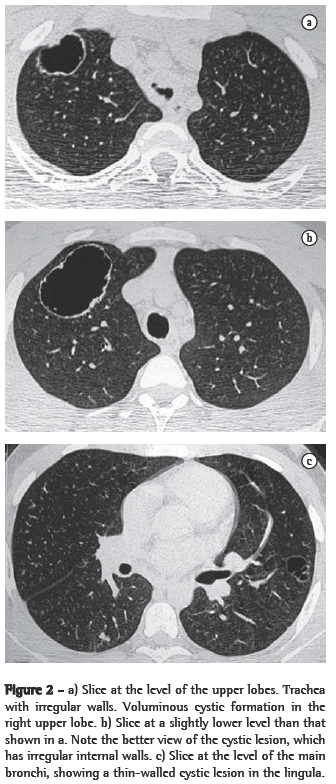

ResultsIn all eight cases, the CT scans revealed polypoid formations in the trachea. In one case, injury to one of the main bronchi was identified. Seven patients presented involvement of the pulmonary parenchyma. In all eight cases, there were cavitated polypoid lesions, with irregular internal borders and walls of various thicknesses, multilobulated in six cases and presenting confluence of the lesions in five (Figures 1 through 5). Solid nodules were seen in six patients. An air-fluid level was observed in only one patient. The lesions were predominantly in the lung bases in three patients and in the middle thirds in two, whereas they were evenly distributed in two. In one patient, the lesions were accompanied by a mass, and, in another patient, they were accompanied by consolidation. In the latter case (Figure 5), there was malignant degeneration in multiple lesions. Signs of air trapping were also observed in one case. There were no identified instances of lymph node enlargement or pleural effusion.

Chest X-rays are inferior to CT scans of the chest, especially those performed using spiral CT (volumetric acquisition), in the initial phases of pulmonary dissemination, due to the fact that CT better characterizes and allows better visualization of nodular tracheobronchial vegetation, Tomographic findings include focal or diffuse airway narrowing caused by the nodules. The nodules form on the mucosal surface, and their invasion into the lumen is best evaluated using CT.(3) These alterations are easily correlated with the disease when there is a clinical history of papillomatosis.(4) Other findings related to airway obstruction and accompanying infections are atelectasis, consolidations, air trapping and bronchiectasis.(2-4) In our sample, polypoid formations in the trachea were observed on all of the CT scans Seven patients presented involvement of the pulmonary parenchyma, characterized by cavitated polypoid lesions with irregular internal borders and walls of various thicknesses, with a multilobulated aspect and a tendency toward confluence. Solid nodules were seen in six patients. None of the patients presented lymph node enlargement or pleural effusion.